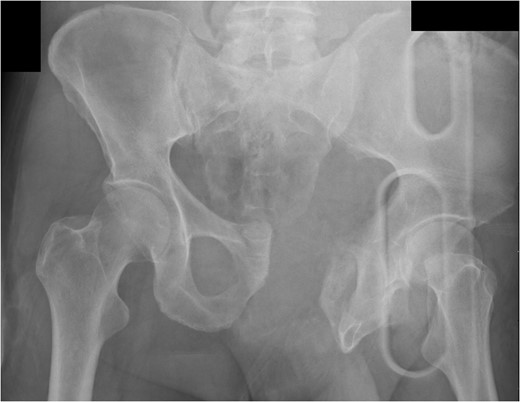

Patients who present hemodynamically unstable from complex pelvic fractures continue to be extremely challenging. Exactly which procedure should be used, and in which specific patients, is still vague and somewhat unclear from the extant literature. We propose the following algorithm based on the literature and our experience (Fig. 4).